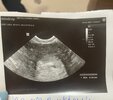

Halo ciocie ? Jestem tu i mam 4 mm 🥹❤️

Załączniki

• 9F299A35-11A4-4088-A763-4B87F795F829.jpeg

9F299A35-11A4-4088-A763-4B87F795F829.jpeg

189,1 KB · Wyświetleń: 116